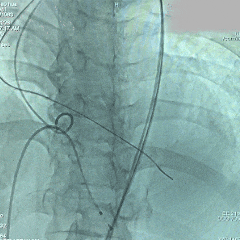

回收后再次释放

第二次展开造影,瓣膜位置尚可,基本无漏

多角度评估,瓣膜深度可

脱钩释放

脱钩后,瓣膜无位移

造影评估,瓣膜深度可,无瓣周漏

左头观察,腰征明显,锚定稳定

术后TEE评估

TEE超声评估微量瓣周漏,测压差7mmHg,反流改善明显。